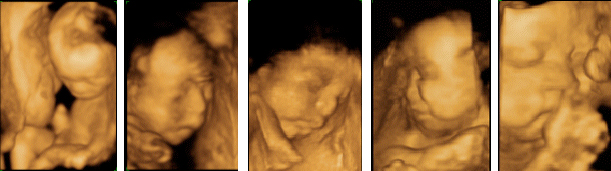

従来の4D画像

当クリニックの4D画像(Voluson S8)

※ 掲載している画像は、「妊娠20週〜37週の胎児4D画像からの一例(当クリニックでの実際の症例)」です。